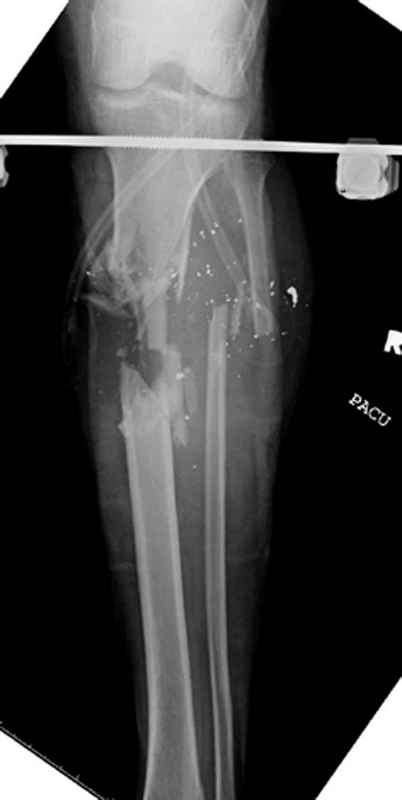

огнестрельный перелом голени

Здесь представлен больной 27 лет с ранениями, включая огнестрельный перелом большеберцовой кости.

11.08.09 доставлен в операционную, Irrigation&Debridment c фиксацией Наружным Фиксатором и вакуумирование VAC; службой травмы пройзведена ангиография с негативным результатом. (снимки 1-10)

14.08.09 повторная Irrigation&Debridment (чувстительственность из раны негативная) со сменой фиксации на медуллярный гвоздь и вакуумирование VAC

18.08 и 21.08.09 Irrigation&Debridment с сменой е VAC, после высеялся MRSA in thio т.е. на специальных срезах небольшое количество (11-13)

25.08.09 повторная Irrigation&Debridment. Пластик хирург не стал рисковать с Soleus flap из-за отечности, и применен Gastric flap, кожная пластика на медиальную и латеральную рану; аллографт из костных стружек с BMP. Поверхность вакуумирована VAC системой на 4 дня (14-16)